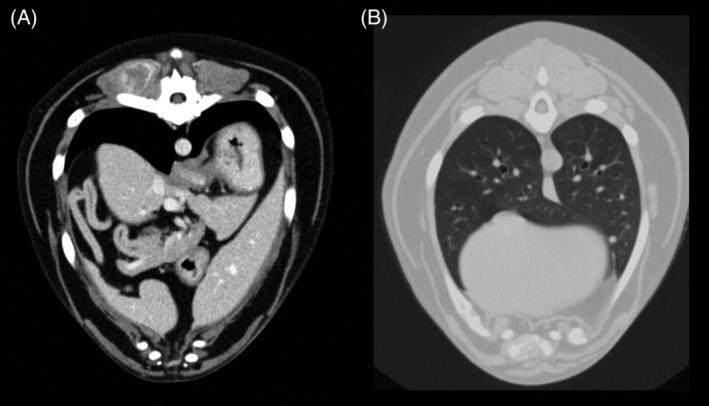

Retrospective study. Dogs with a final diagnosis of visceral or muscular HSA that underwent whole body CT scan were enrolled in the study. Final diagnosis of primary tumor and SMMs was reached by histology, cytology, or both. Signalment, clinical signs, localization of the primary lesion, and metastases characteristics were reviewed.

Sixty-one dogs met the inclusion criteria. Skeletal muscle metastases were detected in 15 dogs (24.6%) and all of these dogs had also metastases in ≥1 sites. Presence of SMMs was significantly higher in males but was not significantly related to age, neuter status, breed, localization, and dimensions of the primary tumor. Nine of 15 (60.0%) dogs with SMMs showed lameness or reluctance to move whereas these signs were not recorded in any of the 42 dogs without SMMs (P < .001).

Prevalence of SMMs in our population of dogs with HSA was higher in comparison to previous studies in the human and veterinary medical literature. Whole body CT is recommended for staging of dogs with HSA, because SMMs could be missed by clinical examination and traditional diagnostic imaging modalities.